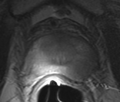

Prostate cancer is a kind of common cause of cancer in men in many countries. Transrectal ultrasound (TRUS) is the most commonly used modality for guiding needle biopsies and minimally-invasive surgical interventions for the treatment of prostate cancer. However,it is difficult to accurately distinguish tumors in B-mode TRUS images. Magnetic resonance (MR) is a very promising technique for prostate biopsies and prostate interventions. Disadvantages of MR-guided prostate biopsies and prostate interventions are that MRI is an expensive method and not widely available. MR-Ultrasound registration can improve TRUS imaging and take advantages of both modalities. The object of this project it to develop a method of MR-Ultrasound image registration for prostate intervention.